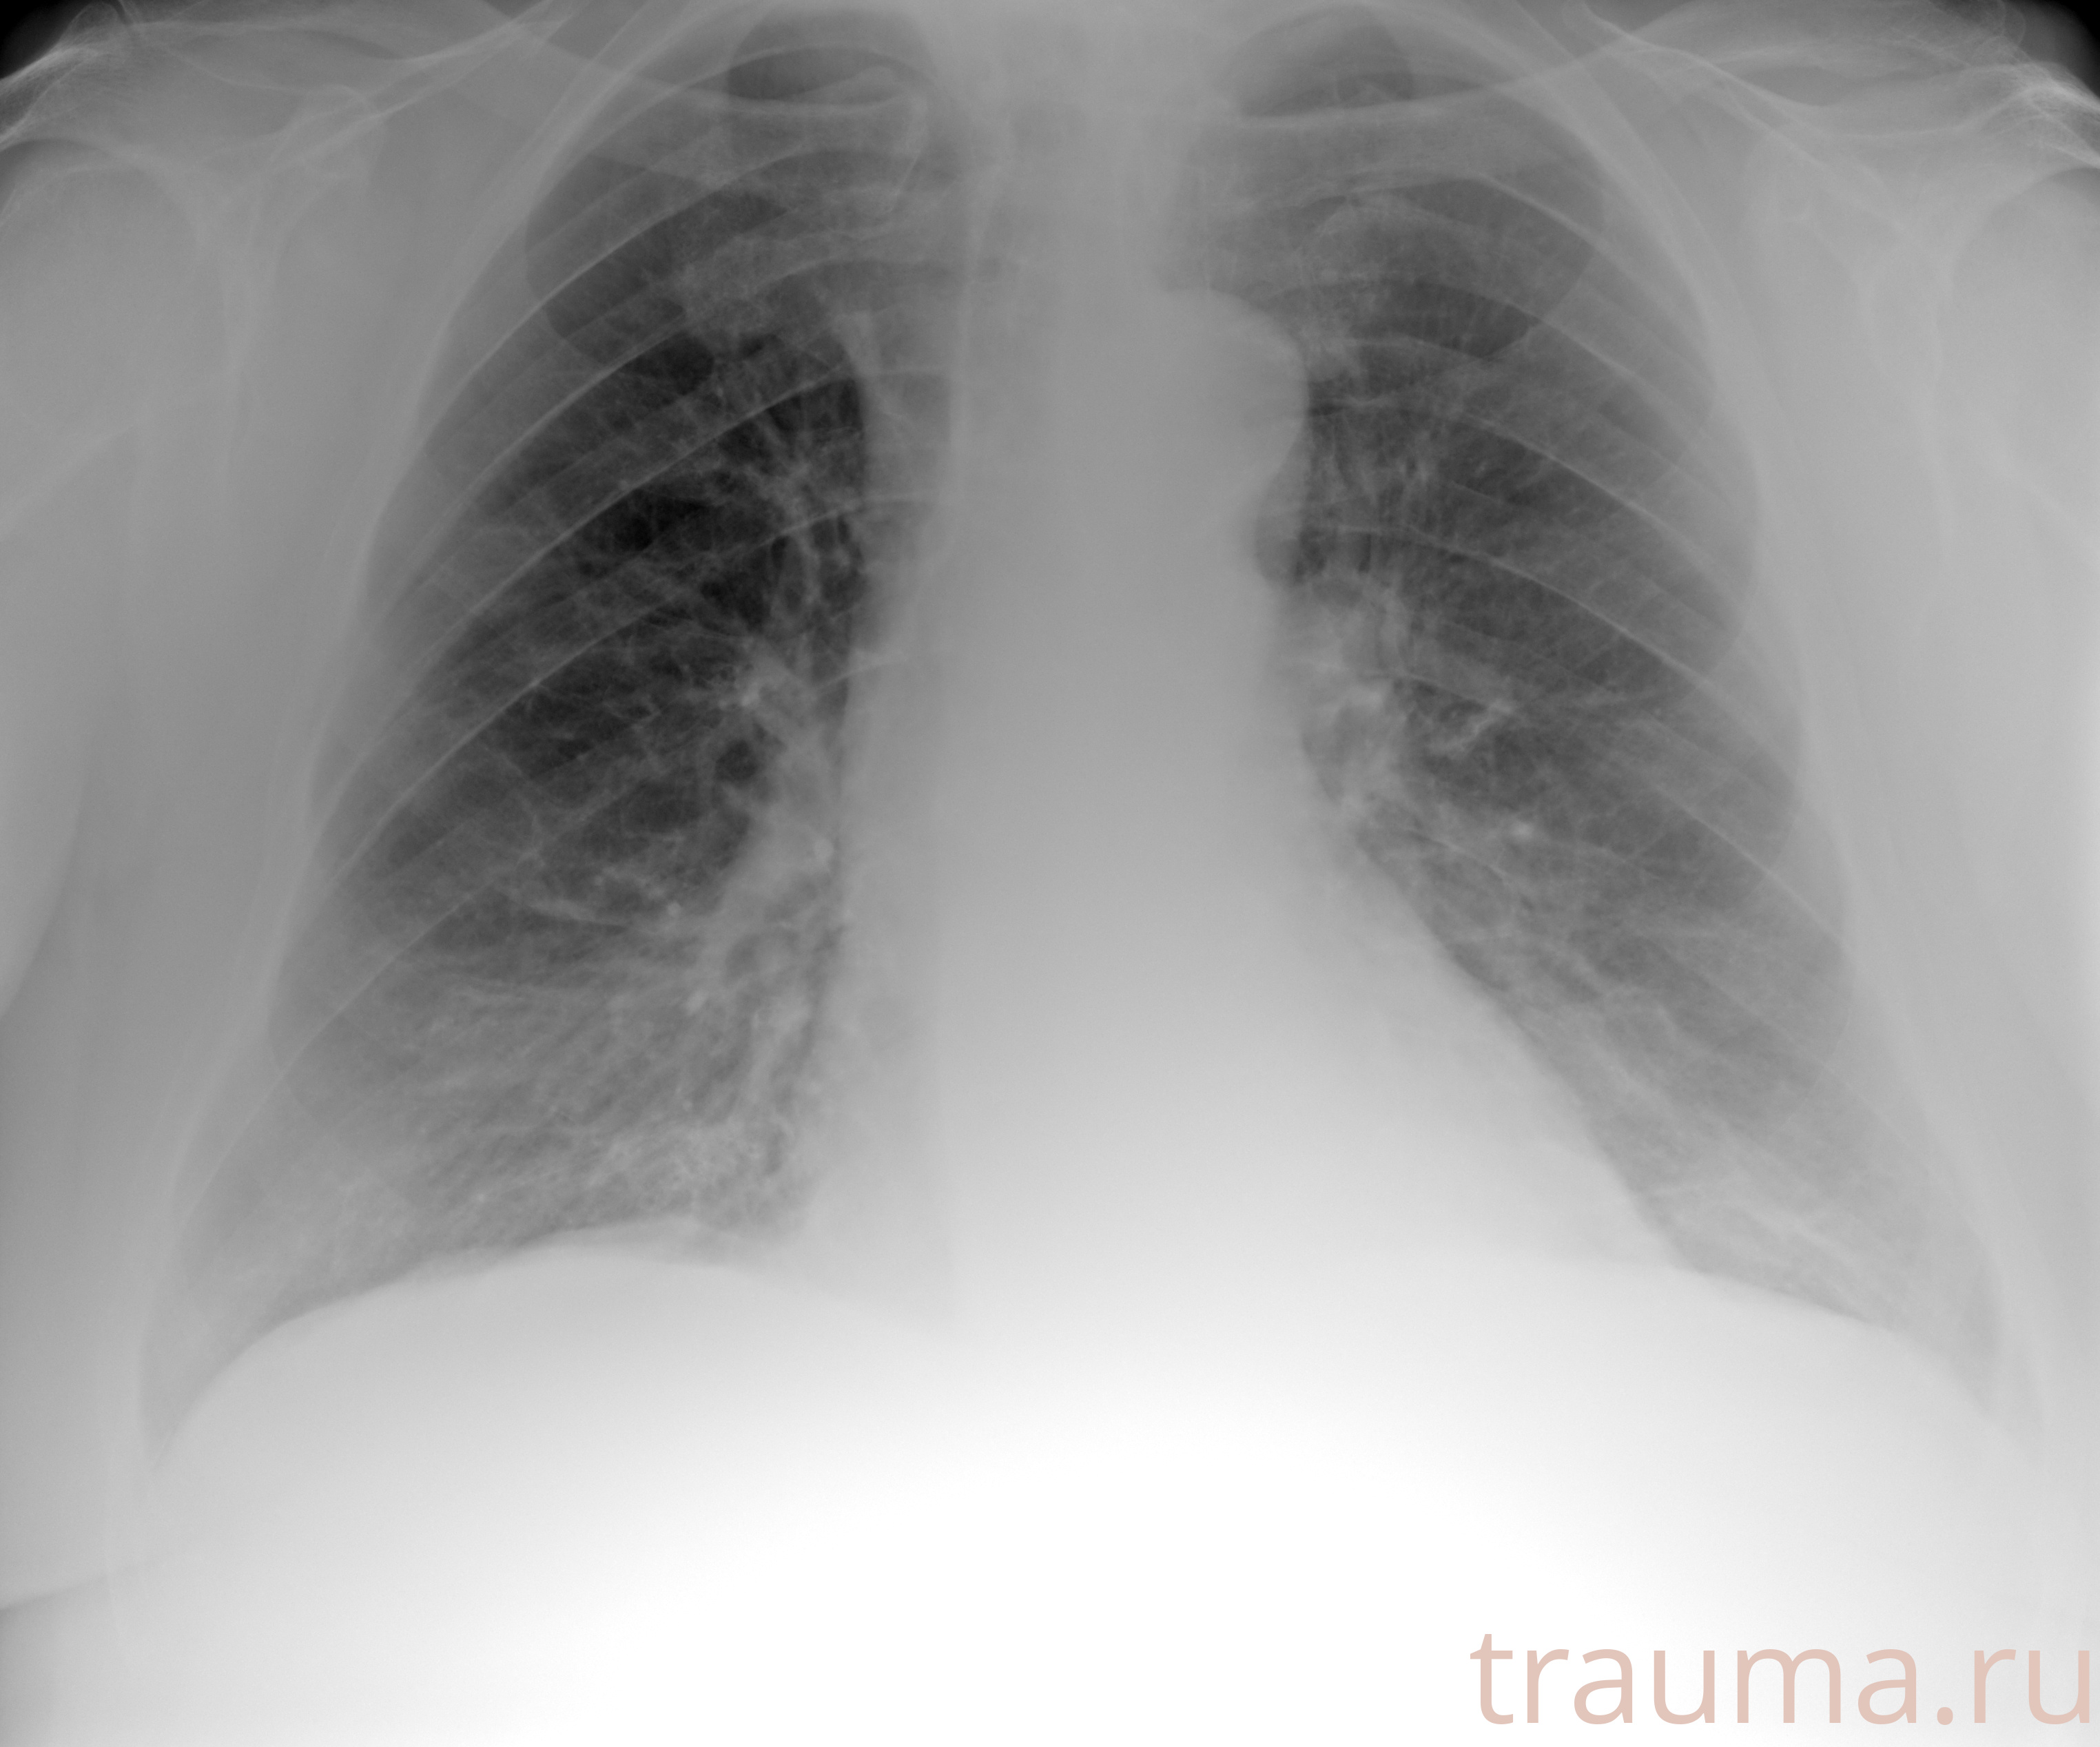

Рентгенограммы

Рентген на дому: по вашему адресу приезжает врач-рентгенолог, травматолог-ортопед с мобильным рентгеновским аппаратом, проводит диагностику травмы или заболевания, делает необходимые рентгенограммы, дает рекомендации по дальнейшему лечению. Получить качественные снимки в домашних условиях возможно благодаря уникальной методике, разработанной МосРентген Центром для института  Склифосовского